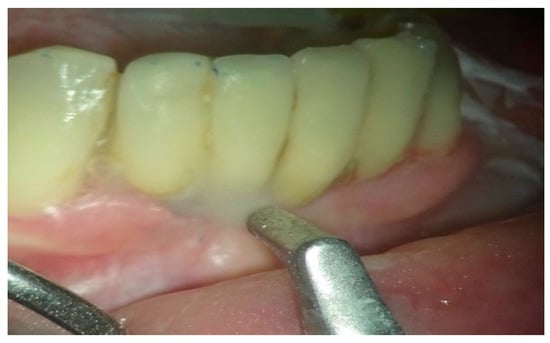

In group B, treated with the OHLLT protocol, a microbiological sampling of the periodontal pockets was made first. Then a supra and subgingival scaling with high-frequency ultrasound was made with a solution of Betadine diluted at 10% (Figure 1). An airflow session with erythritol was performed (Figure 2), and then diode laser treatment with a Sioxyl® solution was performed, irrigating the periodontal pockets with the Sioxyl® solution (Figure 3), leaving the solution for at least 2 min and irradiating with a Wiser diode laser with a peak power of 2.5 W, T-On of 20 microns, T-Off of 80 microns, average power of 0.5 W, duty cycle of 100 microns and frequency of 10 KHz (Figure 4).

Figure 2.

Airflow with erythritol, a low-abrasive powder.